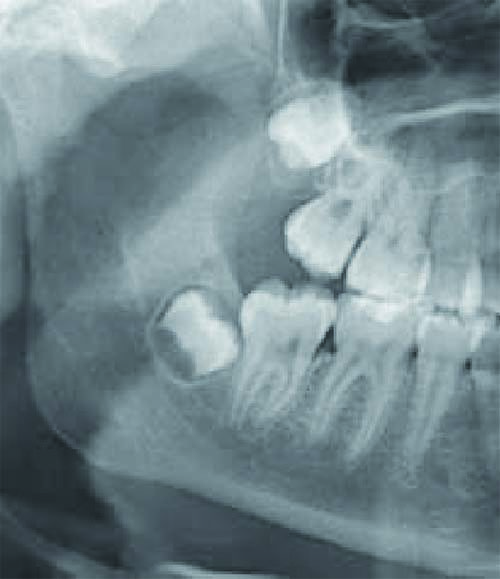

Abbildung rechts

rechte Abbildung: Zahnkeime von Weisheitszähnen im Ober- und Unterkiefer. Der unmittelbar hinter dem Zahn erkennbare Unterkieferknochen lässt erwarten, dass später nicht ausreichend Platz zur Einstellung des Zahnes vorhanden sein wird.